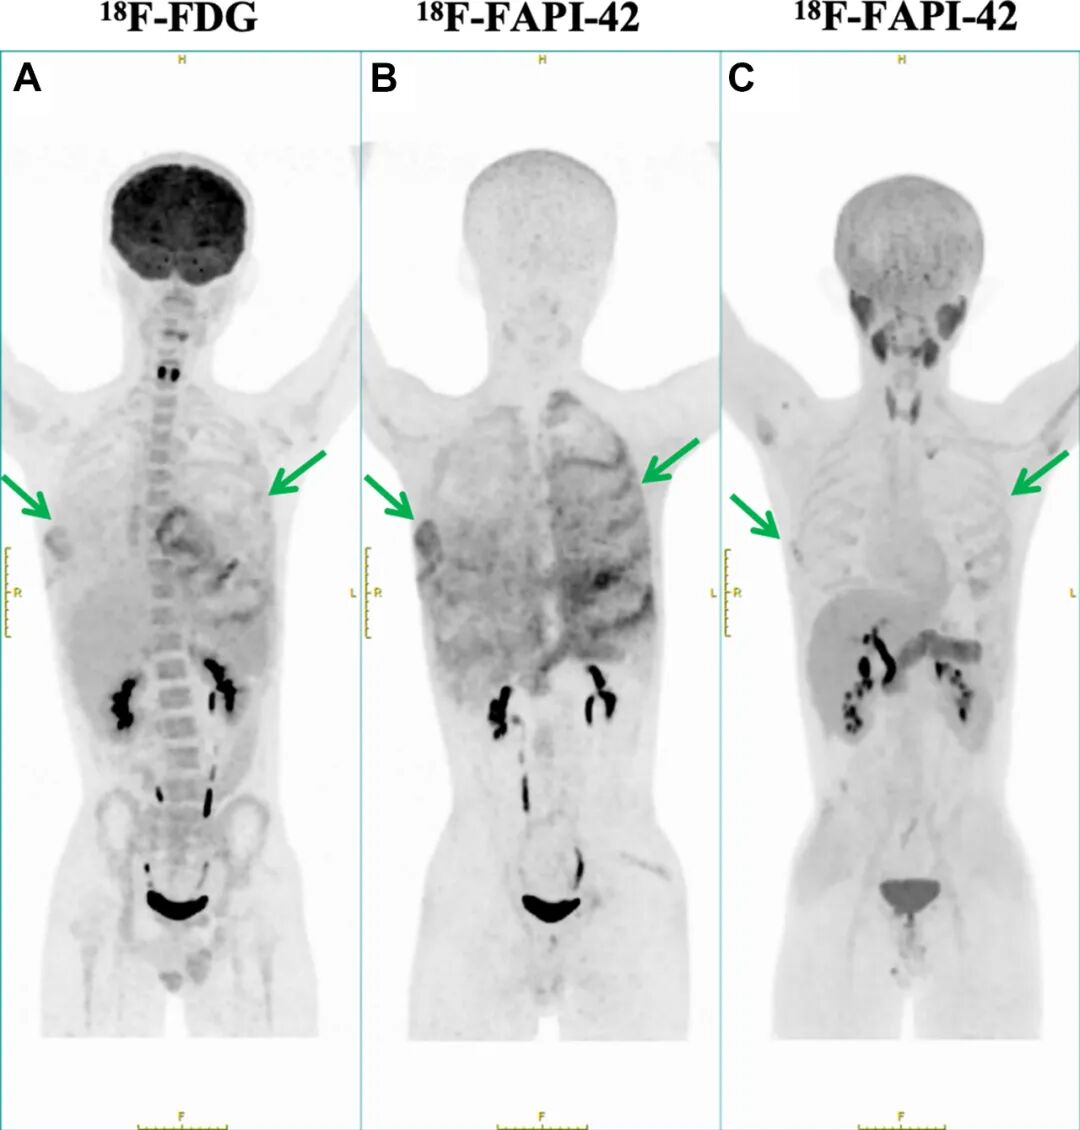

图2. A-C该患者接受了¹⁸F-FDG和¹⁸F-FAPI-42两种示踪剂的PET/CT显像。A¹⁸F-FDG PET/CT显像显示骨质流失区域呈轻度摄取,提示存在高糖代谢区域。B相比之下,¹⁸F-FAPI-42 PET/CT显像则显示出更高的特异性,凸显了受累骨骼内广泛的纤维化活性。C经过1年随访评估,¹⁸F-FAPI-42 PET/CT显像显示胸腔积液减少,且双侧胸膜、心包及骨骼(包括肋骨、脊柱和骨盆)的示踪剂摄取均显著降低。箭头指示示踪剂摄取的特异性区域。¹⁸F-FDG = 氟-18氟代脱氧葡萄糖;¹⁸F-FAPI-42 = 氟-18成纤维细胞活化蛋白抑制剂-42。

治疗12个月后,随访¹⁸F-FAPI-42 PET/CT扫描显示肋骨(SUVmax,2.1)、心包(SUVmax,1.8)和双侧胸膜(SUVmax,2.0)内的放射性示踪剂摄取显著减少,表明成纤维细胞活性受到抑制(图2C和图3C)。胸部超声扫描显示胸腔积液量减少80%,下肢水肿完全消退。重复实验室检查显示CRP(2.1mg/L)和碱性磷酸酶(63U/L)恢复正常,进一步证实了疾病静止。患者在1年随访时已恢复全部学业活动,且报告无功能受限。

2.¹⁸F-FAPI-42 PET/CT成像在检测纤维化活性方面优于传统氟代脱氧葡萄糖成像,可作为诊断和治疗监测的关键工具。